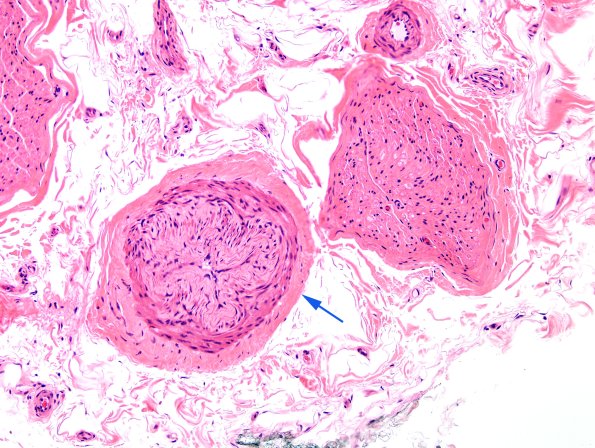

A common vascular appearance in which the wall appears particularly thickened or occluded (arrow) may follow fixation-induced spasm or adjacent crush induced intussusception rather than angiopathy. (H&E)